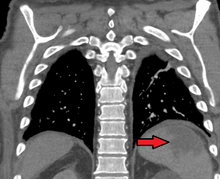

| Splenic infarct seen on CT | |

Splenic infarction is a condition in which oxygen supply to the spleen is interrupted, leading to partial or complete infarction (tissue death due to oxygen shortage) in the organ.[1]

Splenic infarction occurs when the splenic artery or one of its branches are occluded, for example by a blood clot. Although it can occur asymptomatically, the typical symptom is severe pain in the left upper quadrant of the abdomen, sometimes radiating to the left shoulder. Fever and chills develop in some cases.[2] It has to be differentiated from other causes of acute abdomen.

An abdominal CT scan is the most commonly used modality to confirm the diagnosis,[2] although abdominal ultrasound can also contribute.[3][4][5]